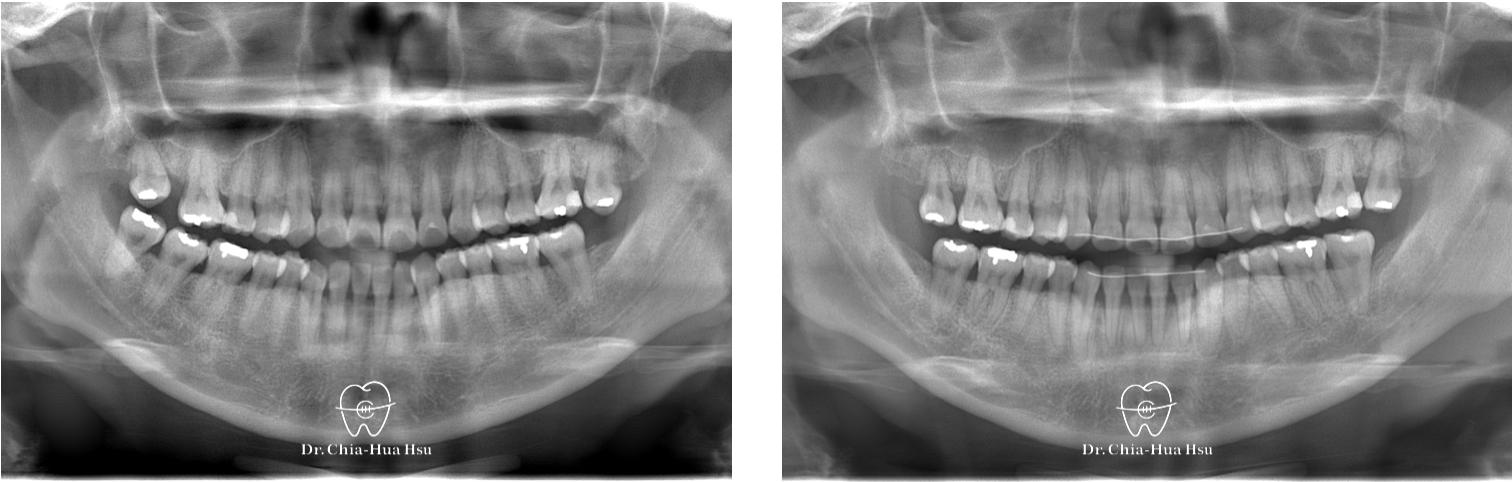

錯咬、齒列擁擠

成人矯正 | ⾦屬矯正 | 非拔牙治療 | 骨釘

治療前

治療後